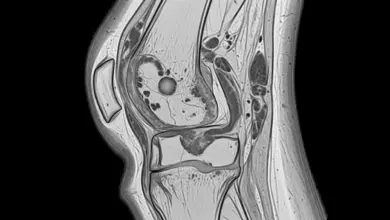

Para um diagnóstico de uma fratura no joelho, após a investigação inicial dos sintomas, é fundamental procurar um ortopedista.

Esse especialista realizará um exame físico detalhado e solicitará exames de imagem, como raios-X, para confirmar a presença de fratura.

Em algumas situações, podem ser necessários exames mais complexos, como tomografia computadorizada ou ressonância magnética, para uma avaliação mais precisa das lesões ósseas e de tecidos moles.